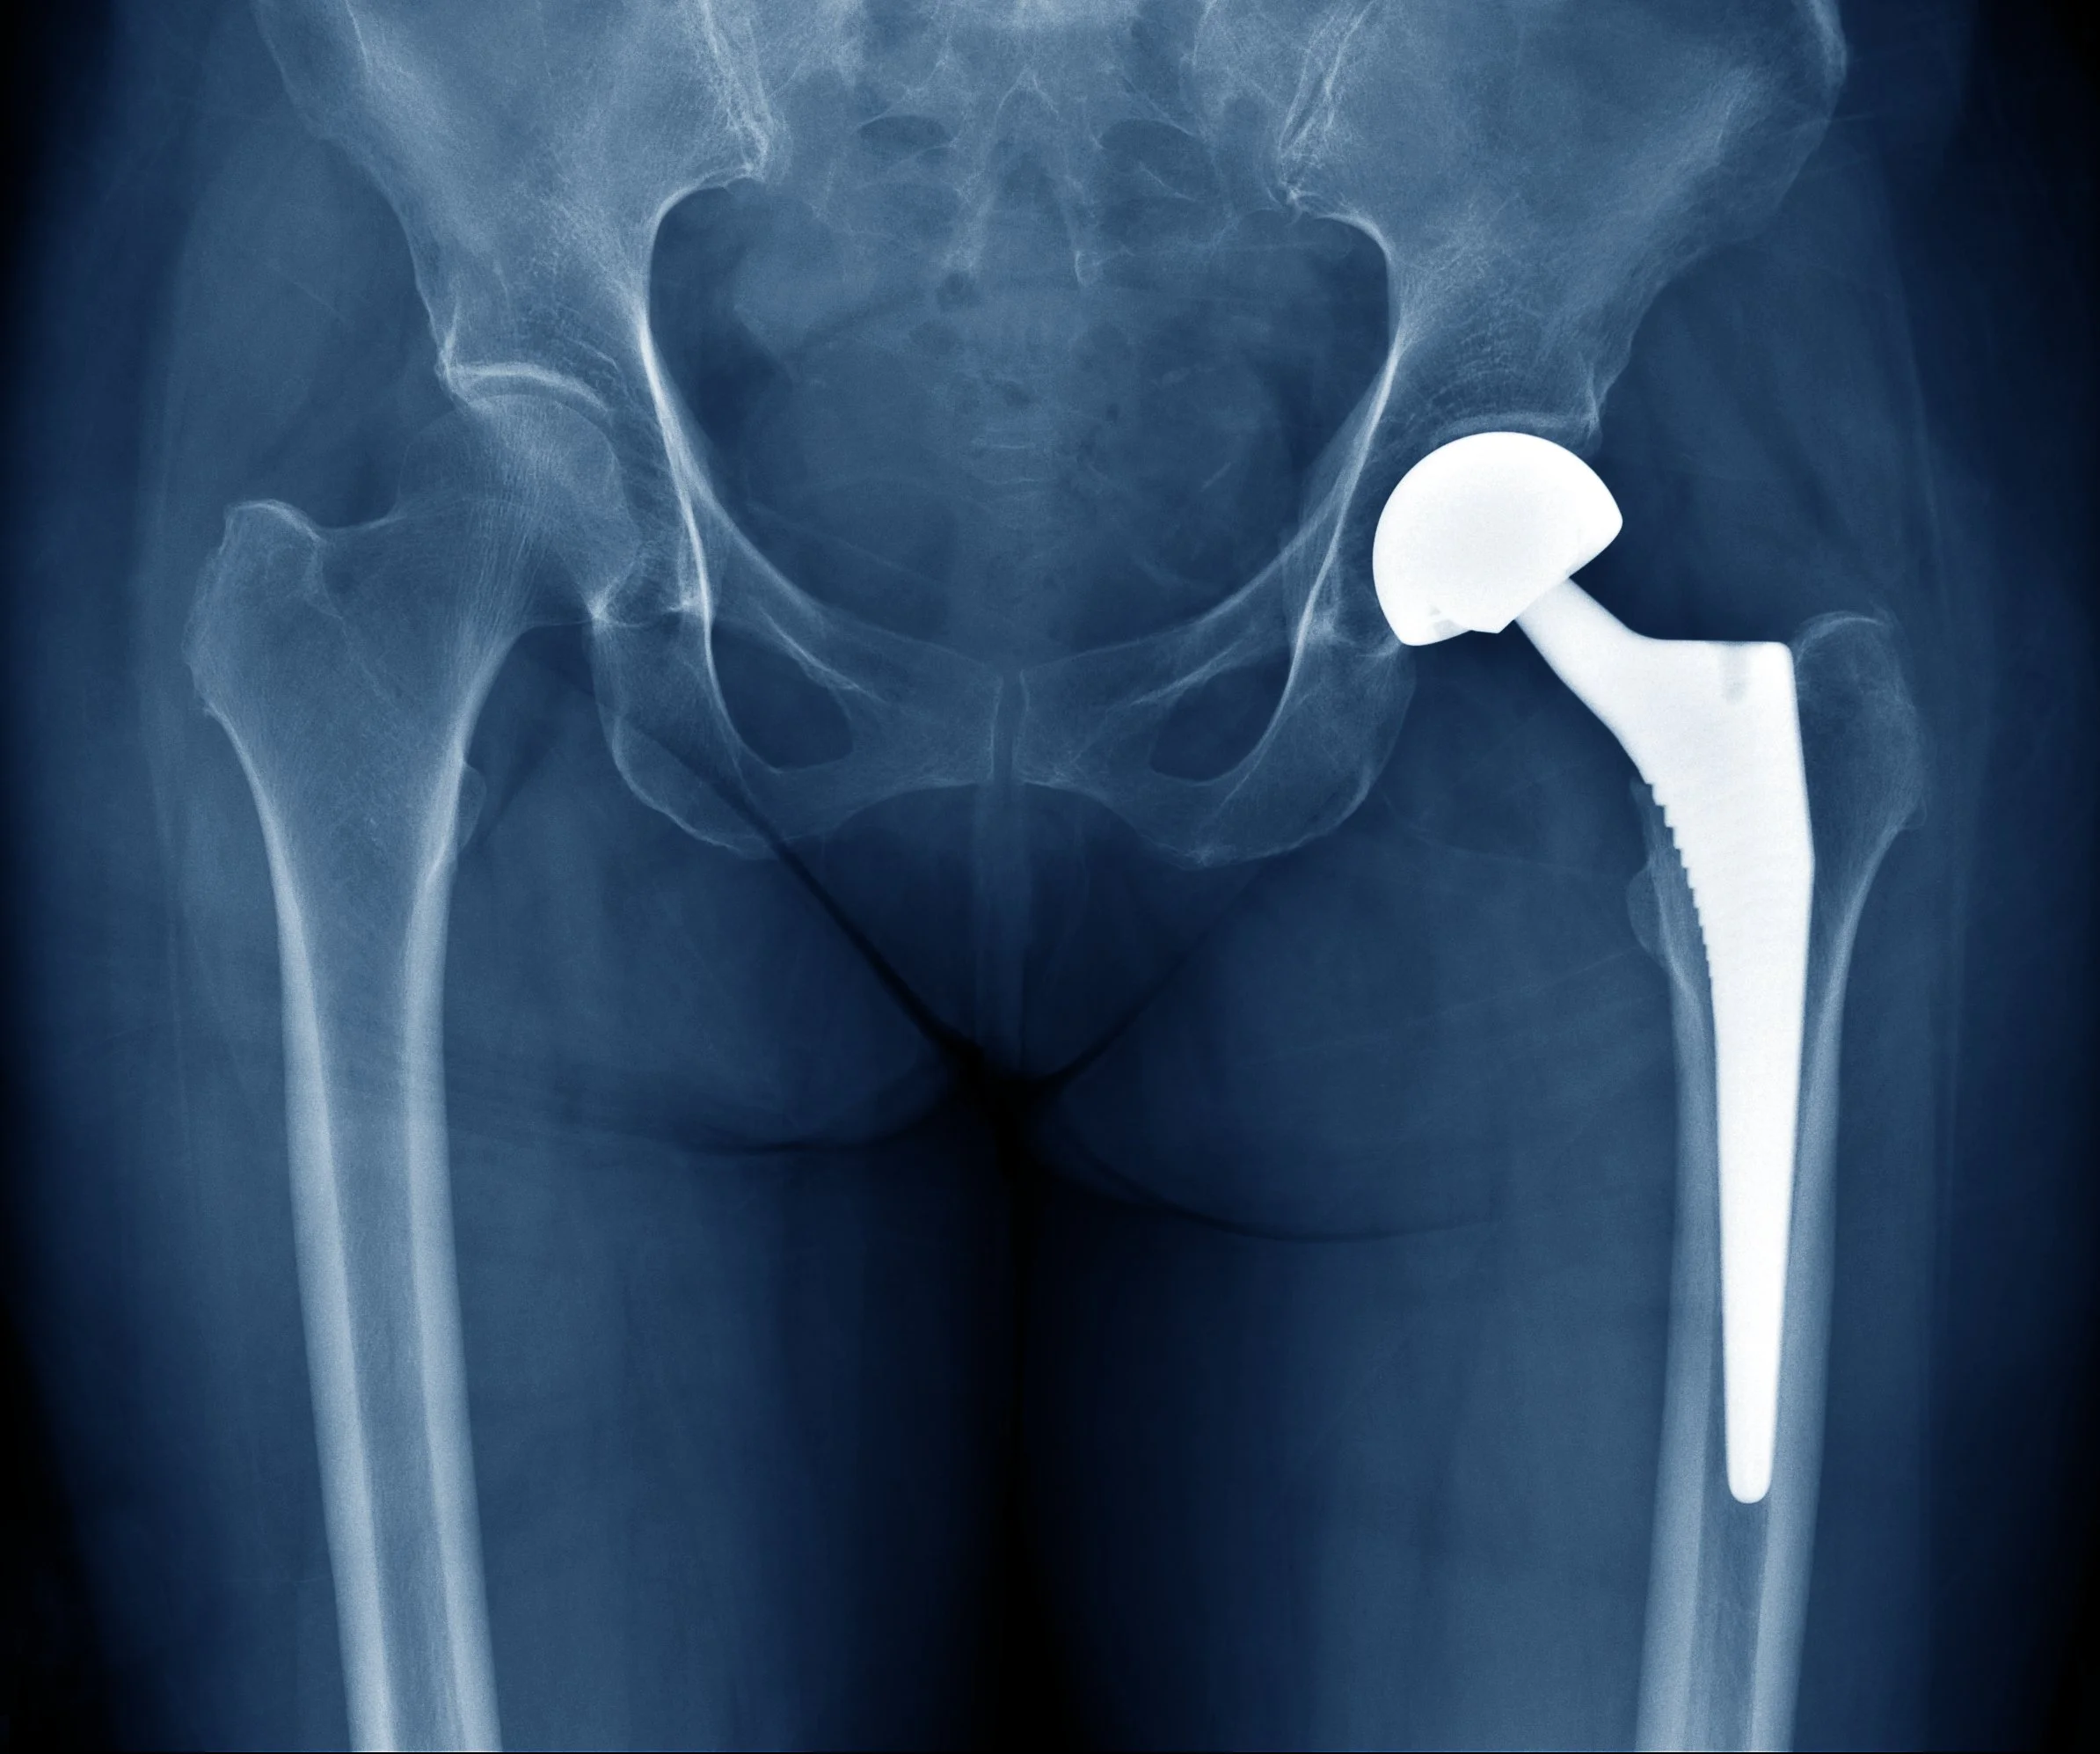

Dr. Evans completed his fellowship in joint replacement surgery at the Cleveland Clinic Florida. There, he trained in joint replacement and complicated revision surgeries. He also gained expertise in advanced robotic procedures.